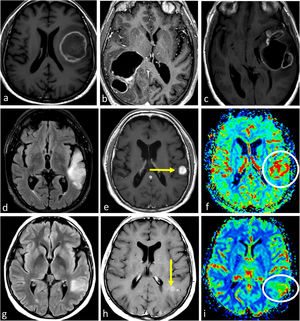

ImágenesEstos tumores suelen mostrar predilección por los lóbulos frontales. Se manifiestan como lesiones centradas en la corteza y la sustancia blanca subcortical. Su epicentro cortical es característico y a menudo está marcado por un signo típico de «cortex continuo». Este término se refiere a la afectación de la corteza en más de 50% de la extensión del tumor. Con frecuencia se observan calcificaciones (que se detectan mejor con tomografía axial computarizada [TAC]) y quistes; y ambos pueden ser distintivos. Es posible la hemorragia. Estas tres características son infrecuentes en los astrocitomas IDH-mutados. Además, suelen presentar una heterogeneidad prominente en las imágenes en T1w y T2w, con márgenes tumorales mal definidos. En la mayoría de los casos no poseen realce, pero algunos sí lo hacen, posiblemente con mayor frecuencia en el grado 3. Su morfología suele seguir un patrón giriforme a lo largo de la corteza, en lugar del aspecto nodular/redondeado de los astrocitomas con mutación en IDH4,23–27. Además, los oligodendrogliomas muestran patrones más heterogéneos en DWI y DSC-PWI; posiblemente exhiban áreas de CBV más alto y restricción de la difusión34–36 y la gradación basada en imágenes no es fiable24,37 (fig. 8).

Oligodendrogliomas IDH-mutados 1p/19q codeleccionados grado 2-3. a-f) Paciente de 53 años. TAC axial sin contraste (a), T1w (b), T2w (c), FLAIR (d), T1w poscontraste (e) y mapa de color de CBV (f). Masa bifrontal difusa mal definida con extensa infiltración cortical (c y d) y señal heterogénea en T1w y T2w (b y c). Calcificaciones prominentes en TAC (a). Realce irregular muy sutil (flechas en e) y áreas de CBV elevado (círculo en f). g-h) Paciente de 52 años. Axial T2w (g) y FLAIR (h). Masa parietal infiltrante mal definida con señal heterogénea y extensa infiltración cortical (g-h). Presencia de pequeñas áreas intratumorales sin realce con intensidad de señal sugestiva de líquido, compatibles con focos quísticos (flechas en g y h). i-j) Paciente de 38 años. T1w axial (i) y mapa de color de CBV (j). Ejemplo de un pequeño quiste intratumoral en T1w (flecha en i) y CBV claramente elevado (j). k-l) Paciente de 35 años. FLAIR axial (k) y T1w post-contraste (l). Masa infiltrante mal definida e hiperintensa en FLAIR claramente centrada en la corteza y siguiendo su morfología giriforme: signo de cortex continuo (círculo en k). Pequeños focos asociados de realce sólido (flecha en l). Obsérvese también la ausencia del signo de mismatch T2/FLAIR en c-d y g-h.

CBV: volumen sanguíneo cerebral; IDH: gen isocitrato deshidrogenasa; TAC: tomografía axial computarizada.

Según la experiencia de los autores, los gliomas difusos de la línea media con alteración de H3K27M en adultos pueden manifestarse como gliomas clásicos del tronco encefálico, a veces con ciertas características atípicas, que sirven como señales de alarma como, por ejemplo, un realce claro y anomalías en DWI o DSC-PWI. De forma alternativa, estos tumores pueden presentarse en el tronco encefálico o en otras estructuras de la línea media (tálamo) con características claramente agresivas, como realce heterogéneo ávido, restricción de la difusión, CBV elevado, necrosis y hemorragia (fig. 9). Se ha descrito que esta última presentación es más frecuente cuando se han extendido fuera de la línea media estricta72.

Gliomas difusos de línea media H3K27M-alterados. a-c) Paciente de 52 años. FLAIR axial (a), T1w poscontraste (b) y mapa de color de CBV (c). Glioma troncoencefálico, ligeramente paramediano, nodular y bien definido en FLAIR (a), con focos de realce (flecha en b) y CBV ligeramente elevado (círculo en c). d-f) Paciente de 48 años. FLAIR axial (d), T1w poscontraste (e) y mapa de color de CBV (f). Masa infiltrante bitalámica hiperintensa en FLAIR (d) con realces nodulares sólidos multifocales (e) y CBV elevado. g-i) Paciente de 33 años. FLAIR axial (g), T1w poscontraste (h) y mapa de color de CBV (i). Masa talámica hiperintensa en FLAIR con edema extenso (g), realce irregular en anillo grueso con necrosis central (flecha en h) y CBV elevado en la periferia (flecha en i).

CBV: volumen sanguíneo cerebral.